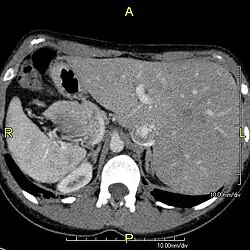

Situs inversus (also called situs transversus or oppositus) is a congenital condition in which the major visceral organs are reversed or mirrored from their normal positions. The normal arrangement of internal organs is known as situs solitus. Many people with situs inversus have no medical symptoms resulting from the condition, although cardiac problems are the most common complication. Until the advent of modern medicine, it was usually undiagnosed.

Situs inversus is found in about 0.01% of the population, or about 1 person in 10,000. In the most common situation, situs inversus totalis, it involves complete transposition (right to left reversal) of all of the viscera. The heart is not in its usual position in the left chest, but is on the right, a condition known as dextrocardia (lit. 'right-hearted'). Because the relationship between the organs is not changed, most people with situs inversus have no associated medical symptoms or complications.[1]

Effect on anatomy

The condition affects all major structures within the thorax and abdomen. Generally, the organs are simply transposed through the sagittal plane. The heart is located on the right side of the thorax, the stomach and spleen on the right side of the abdomen and the liver and gall bladder on the left side. The heart's normal right atrium occurs on the left, and the left atrium is on the right. The lung anatomy is reversed and the left lung has three lobes while the right lung has two lobes. The intestines and other internal structures are also reversed from the normal, and the blood vessels, nerves, and lymphatics are also transposed.

If the heart is swapped to the right side of the thorax, it is known as "situs inversus with dextrocardia" or "situs inversus totalis". If the heart remains on the normal left side of the thorax, a much rarer condition (1 in 2,000,000 of the general population), it is known as "situs inversus with levocardia" or "situs inversus incompletus".

Diagnosis of situs inversus can be made using imaging techniques such as x-ray, ultrasound, CT scan, and magnetic resonance imaging (MRI).[9]